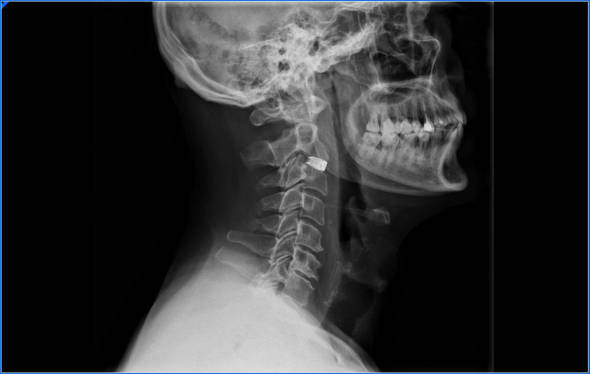

- Radiografía. No son excesivamente útiles. Con una radiografía valoraremos el grado de degeneración y artrosis que tenemos en el cuello.

Artrodesis cervical